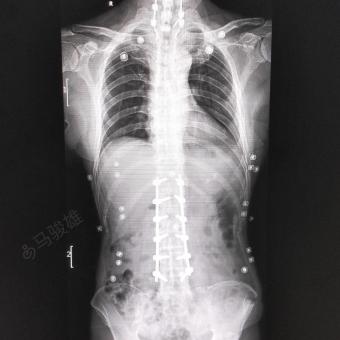

标题:【病例讨论】一例典型的Chance骨折,腰背

640x853 - 29KB - JPEG

640x853 - 26KB - JPEG